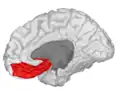

Lateral orbitofrontal cortex

Medial orbitofrontal cortex, inner slice view